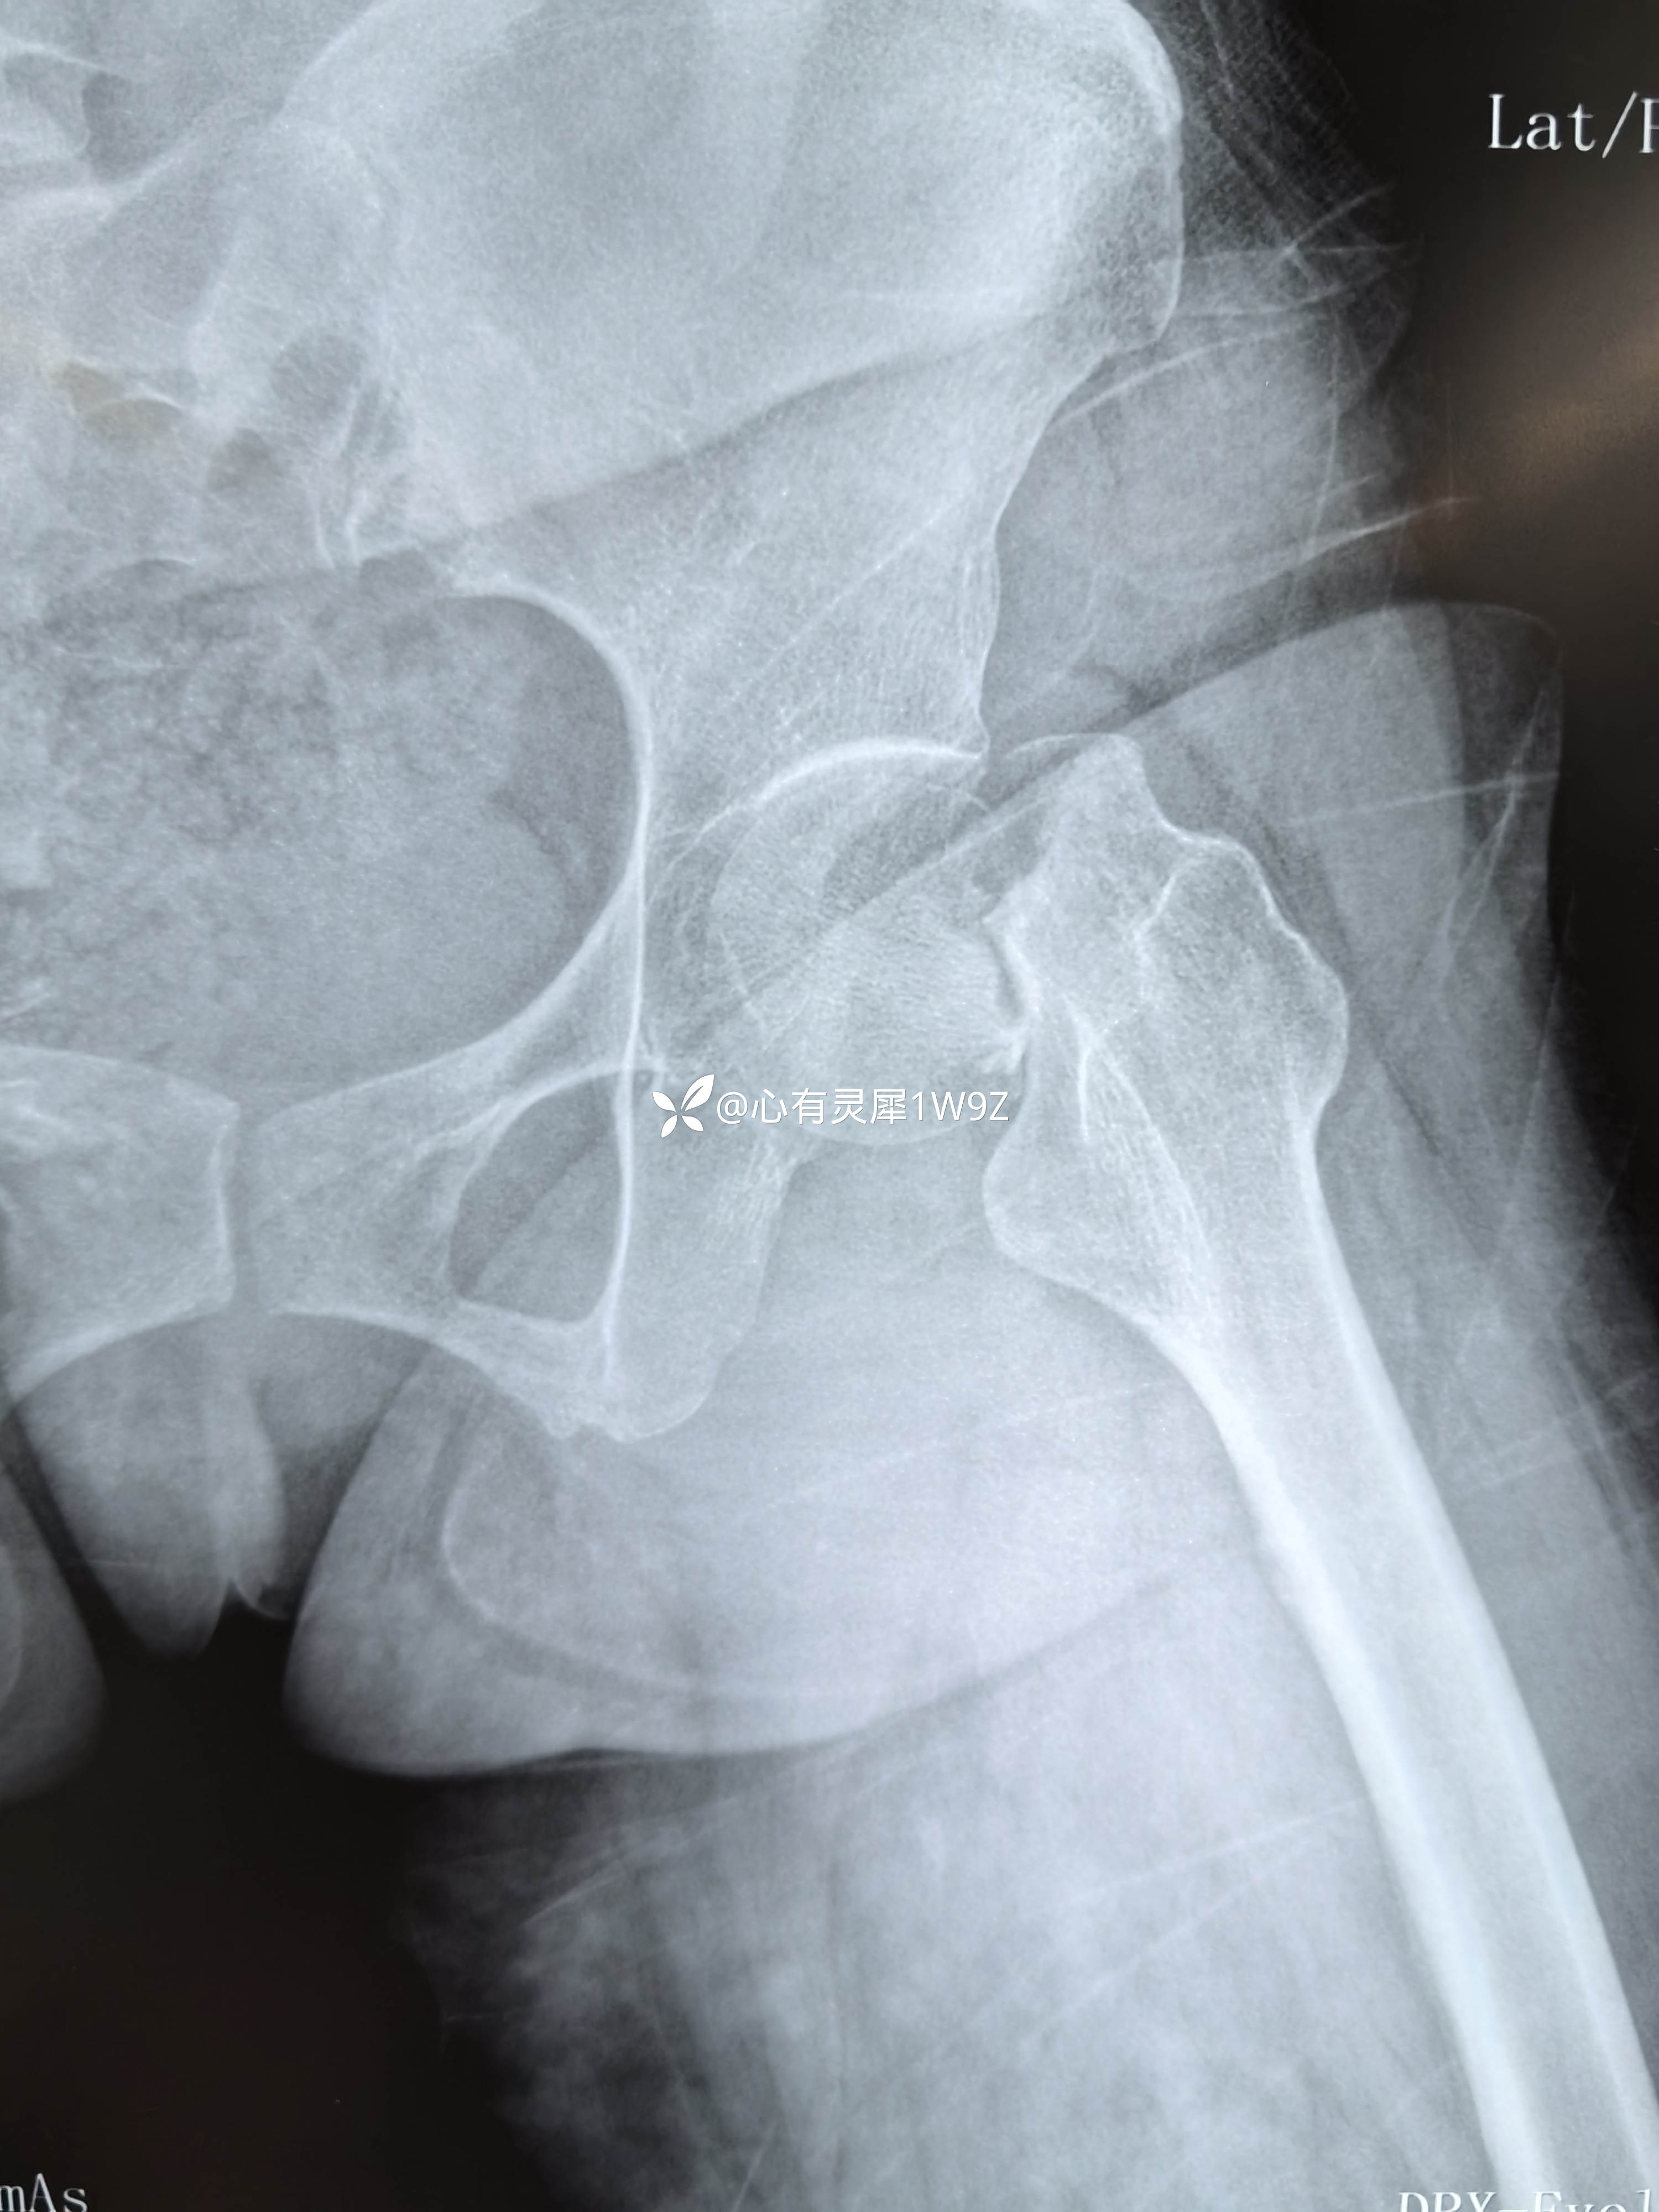

诊断:左侧股骨颈骨折(头下型)garden IV型

2,关于贴壁,平行,长度,角度。自己感觉这次平行和长度都比较满意,贴壁还可以,角度不是很完美,感觉可以接受,就没有再调整。